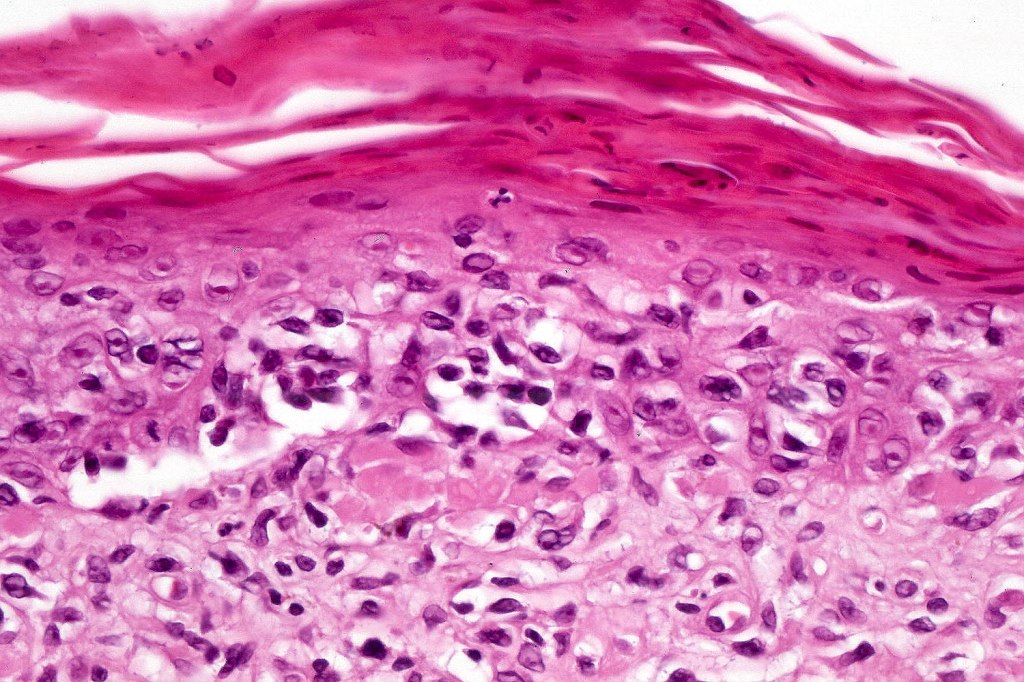

Histological features

The histological hallmark of mycosis fungoides is the presence of large atypical lymphocytes with a convoluted/cerebriform nuclear border (Sézary cells). These may be found at the epidermal-dermal jnuction and as collections within the epidermis (Pautrier microabscess). These are most easily found in plaque stage disease. The epidermal component can be subtle in patch stage disease and is often lost in tumor stage dsease. The classification into patch, plaque & tumor stage disease is less helpful histologically as the features merge from one to the other. It is all a matter of degree.

Tumor Stage Disease

•Epidermotropism is often minimal or absent

•Dense, broad diffuse or nodular, dermal infiltrate often extending into the subcutaneous fat

•Abundant Sézary cells. Frequently accompanied by very pleomorphic forms

•Mitoses often abundant, frequently abnormal

•CD30 expression correlates with transformation (cells X4 size of small lymphocytes comprising 25% or more of the infiltrate or the presence of a distinct large nodule)